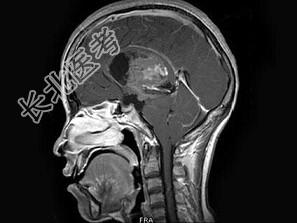

- 单项选择题男,32岁, 头痛呕吐半个月,MRI检查见脑室内占位, 最可能的诊断为 ( )

A、脉络膜丛乳头状瘤

B、室管膜瘤

C、髓母细胞瘤

D、脑膜瘤

E、未见异常